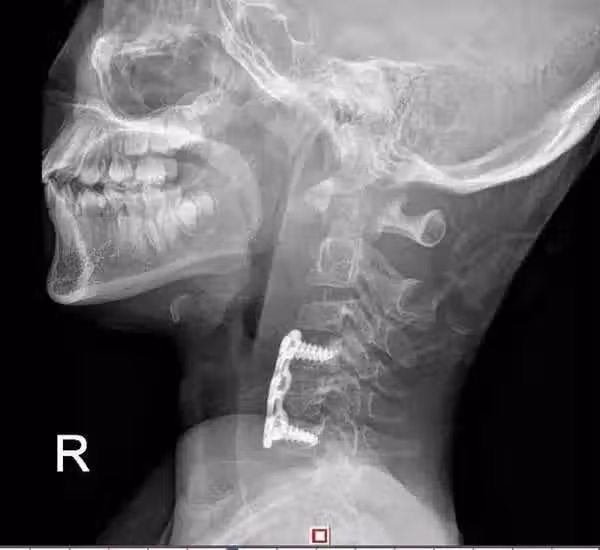

鋼板固定的頸椎側面

鋼板固定的頸椎正面 脊柱外科評估小鵬的病情後給出了手術方案, 最後通過手術把小鵬突出的椎間盤和部分椎體切除,

用鋼板固定了鬆動的椎骨。